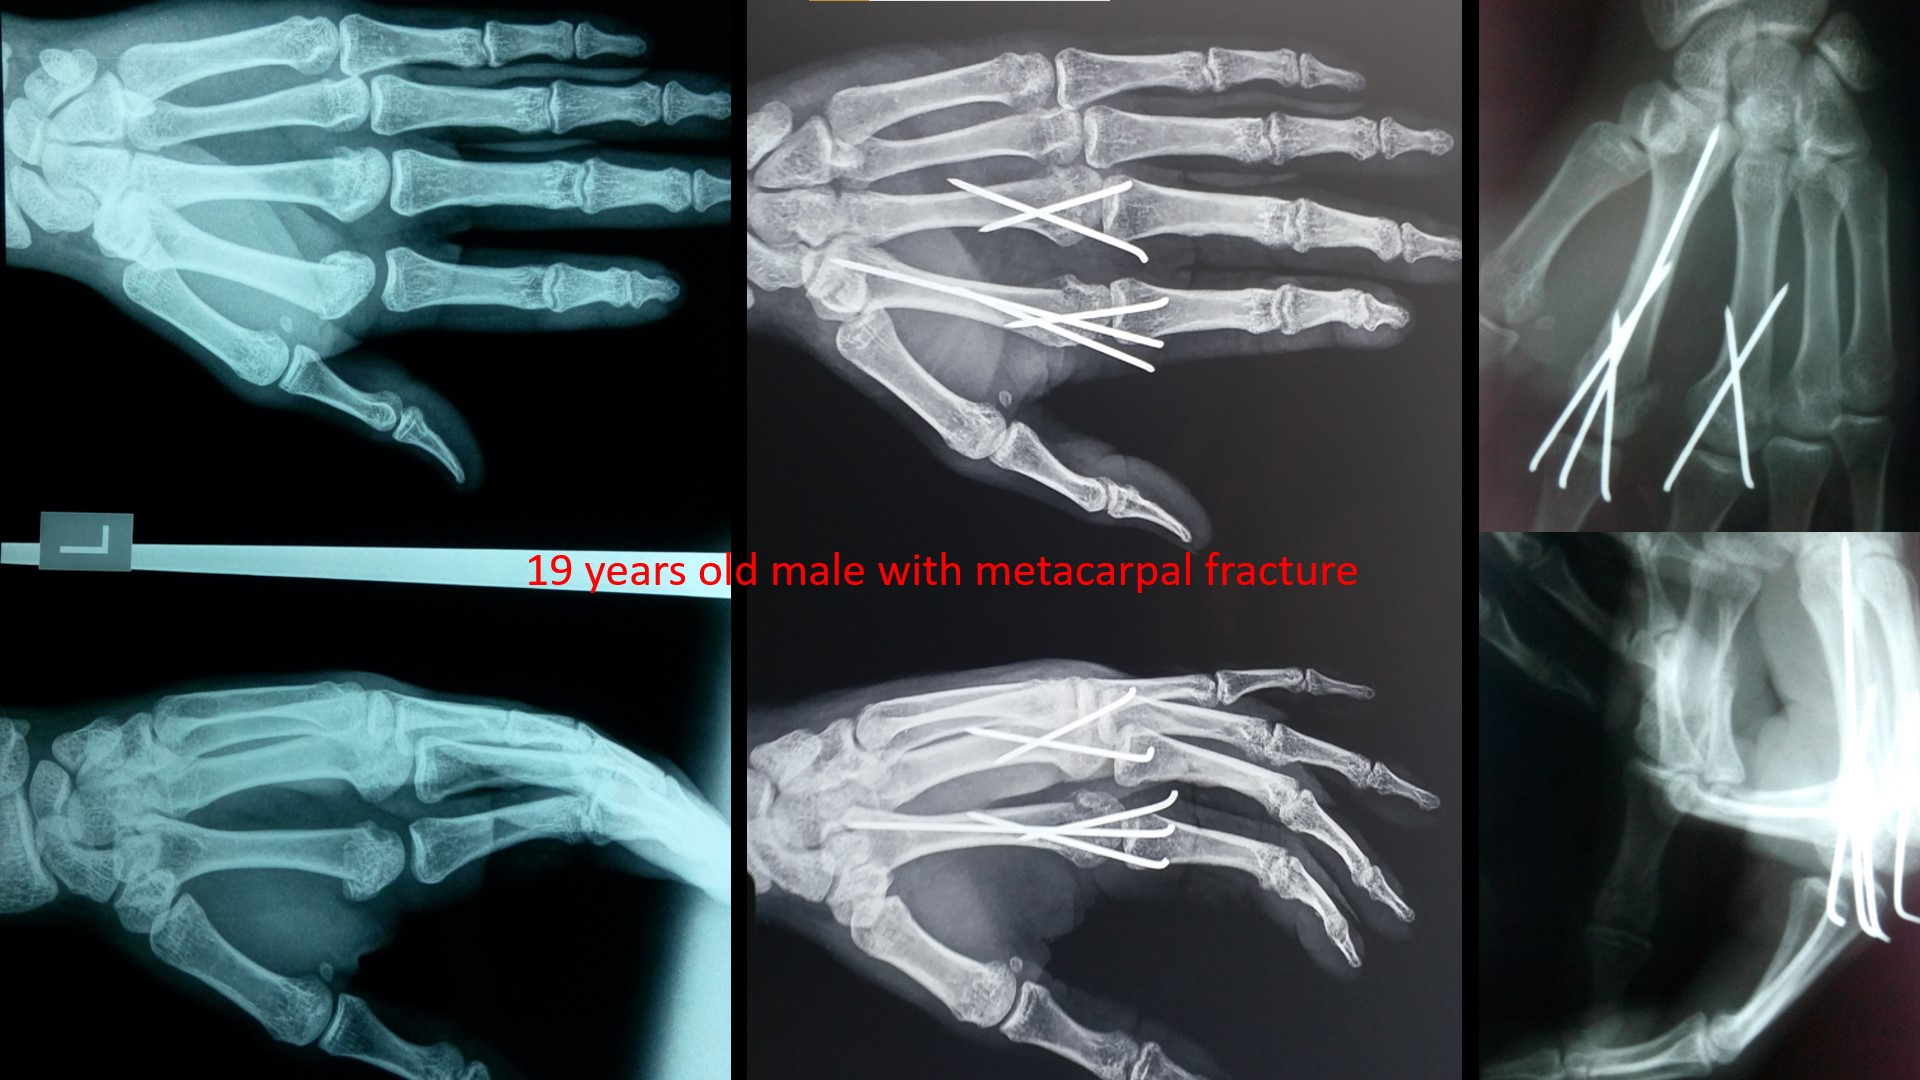

CRPP METACARPAL